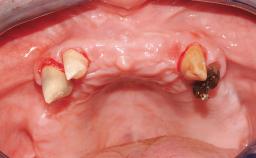

Immediate Loading of Four Implants in the Mandible and Final Restoration with a Full-Arch Metal Framework FDP

A fully edentulous 65-year-old woman was referred to our clinic for esthetic and functional dental rehabilitation. The patient presented with inadequate complete maxillary and mandibular prostheses, insufficient vertical dimension, and extensive tooth wear. The clinical examination and anamnesis showed no local or systemic contraindications, no signs or symptoms of bruxism, and an absence of smoking habits. The treatment proposed was implant placement in the mandibular interforaminal area and immediate loading with a fixed definitive prosthesis. A removable mucosa-supported complete prosthesis was indicated for the upper jaw, since its bone structure offered satisfactory retention and the financial condition of the patient disfavored a full-mouth implant-supported rehabilitation.

Case Type Edentulous Mandible

Jaw Mandible

Area Full-Arch